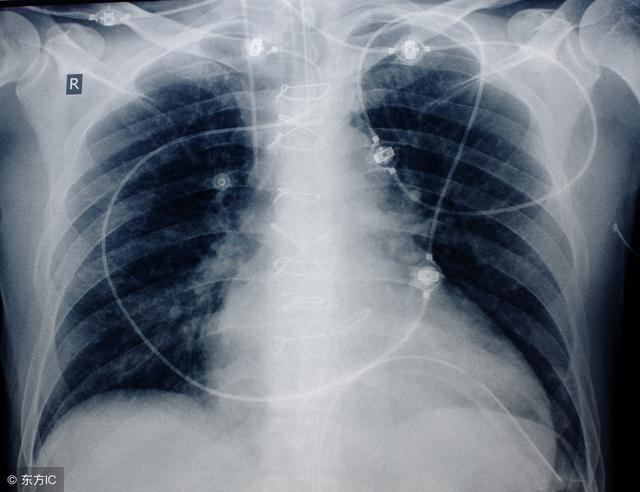

支气管扩张,是以局部支气管不可逆性解剖的异常特征为表现的,该病带来的危害非常大,患者要注意当你患有了这种疾病的时候,必须先要做出检查,检查一下病情发展到了哪一个地步,医生才好根据病情进行治疗,下面详细讲解一下支气管扩张疾病相关知识。

接下来我们来了解一下,鉴别支气管扩张的方法,因为支气管扩张会有很多的症状,所以要想辨别清楚,也是比较困难的,今天我们就来了解一下,如果是慢性支气管炎的话,大部分会出现在中年以上的患者,冬春季节会出现咳嗽,咳痰,还会伴有喘息,多为白色粘液痰,而且发生感染的时候会有浓痰。那么除了这之外,肺结核就会表现出低热,盗汗,全身无力,消瘦等症状,所以每一种症状的不同或是疾病的不同,表现方法又会有所不同,治疗起来也就会不同。